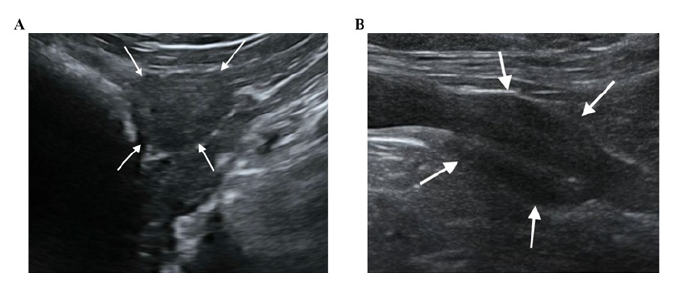

Introducción: La ecografía es el método de elección para evaluar laglándula prostática canina. Si bien estudios recientes han documentadoel papel de la castración en el desarrollo de neoplasias prostáticas,se sabe poco sobre las características del parénquima y laperfusión de la próstata normal y anormal en perros castrados. No hay datos disponibles sobre los cambios prostáticos después de los primeros 90 días tras la castración. El presente estudio tuvo como objetivo obtener datos sobre los cambios ecográficos a largo plazo que se producen en la próstata canina tras la castración.

Materiales y métodos: Diez perros adultos castrados se sometieron a una ecografía en modo B y a una ecografía con contraste (CEUS) de la próstata en dos ocasiones: el día del primer examen (T0) y seis años después (T1). La próstata se evaluó mediante ecografía en modo B y se calculó su volumen utilizando la fórmula de Atalan. Para el examen CEUS, se administró un agente de contraste intravenoso (SonoVue) para evaluar la perfusión prostática. Se grabaron videos y se obtuvieron curvas de tiempo-intensidad para determinar los parámetros de contraste: realce máximo (PPI) y tiempo hasta el pico (TTP). A continuación, se compararon los resultados volumétricos y de perfusión entre los distintos puntos temporales.